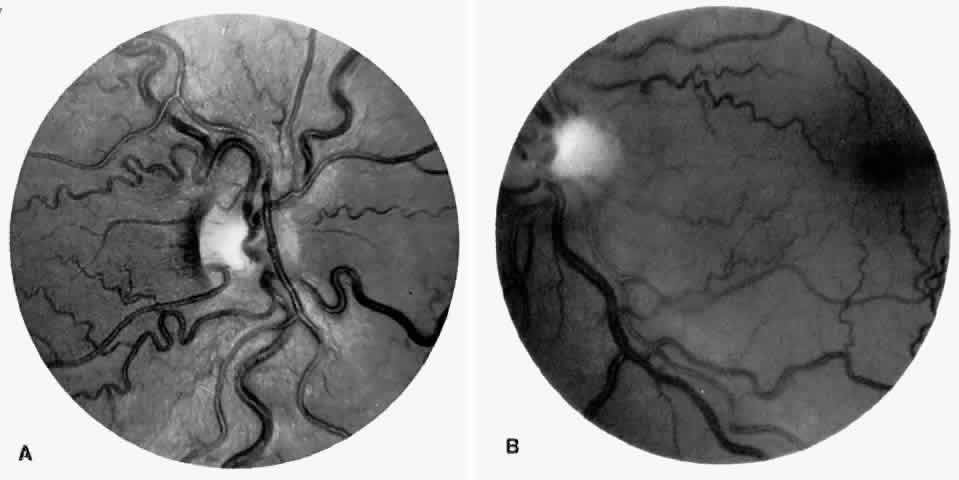

Vascular Tortuosity

Dilation and tortuosity of the retinal veins was one of the first recognized abnormalities of sickle cell eye disease. Although it is not pathognomonic of sickle cell disease, it reportedly occurs in up to 47% of patients with homozygous sickle cell anemia and 32% of patients with SC disease (Fig. 4).70 The significance of this venous tortuosity is unknown, and the incidence does not appear to be related to age.71